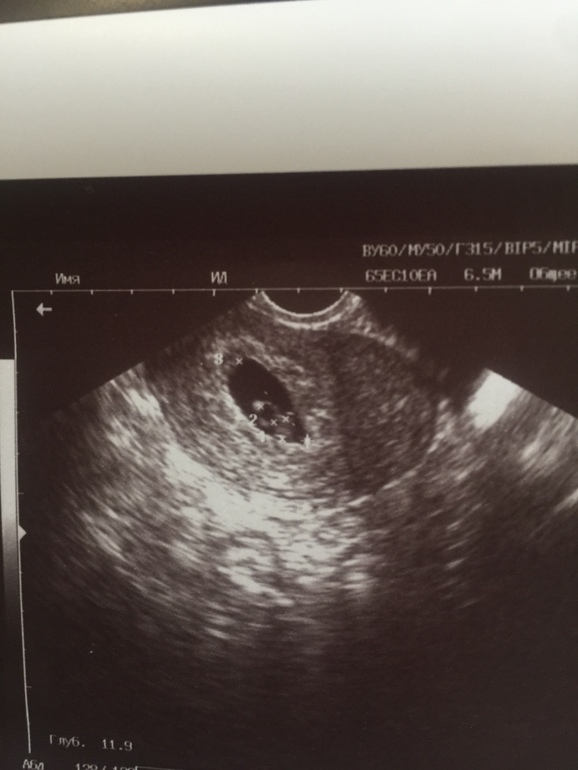

Нашли сердечко!!))

Кто переживал вместе со мной )) нашли сердцебиение, ттт)))) кто переживает так же как и переживала я, почитайте мой дневник, надежда есть всегда !!!

У меня сердечко нашли только ровно в 7 недель, но и по узи срок стоял 7 недель (по размерам), у Вас написали 6,3, так что все в норме у Вас, зря переживали))) Я решила что в след. беременность со вторым пойду на узи после 7 неделек и не буду себе нервы трепать больше))

Спасибо ) ну у меня уже почти 9 акушерских недель, вот и думаю что расхождение большое..)